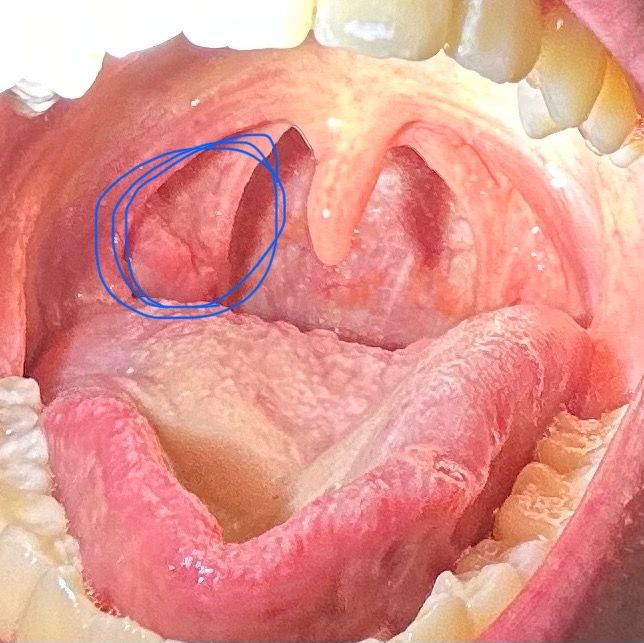

사진상 왼쪽 목구멍부터 목 안쪽까지 아픕니다

이틀 전에 연어를 먹다가 가시를 삼켜서 좀 아픈 것 같아서 신경을 쓰다보니까 진짜 아픈 것 같았습니다. 그래서 다음날 바로 내과에가서 위내시경 검사를 했는데 가시도 없고 이상도 없다고 해서 이비인후과에 가서 목구멍을 봤는데 가시는 없고 염증이 있다고 해서 약을 받아서 먹고 있습니다. 근데 점점 침과 음식을 삼키기 힘들어지고 침삼킬때 귀도 아프고 턱도 뭔가 불편해져서 걱정이 됩니다. 그래서 입 안을 사진을 찍어봤는데 어떤 병인것 같나요?? 가시가 있을 가능성이랑 심각한 병일 가능성이 있을까요???

• 2번 째 사진